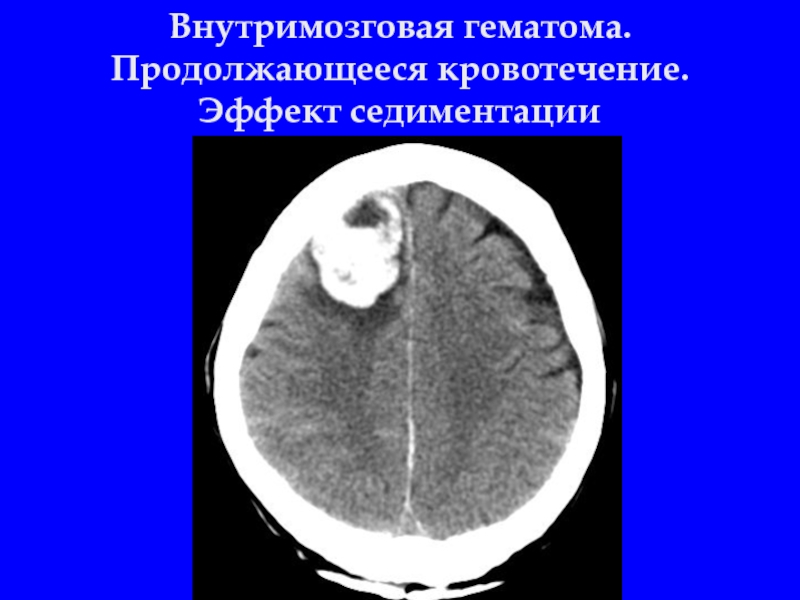

Слайд 23Внутримозговая гематома

Слайд 24Внутримозговая гематома. Продолжающееся кровотечение. Эффект седиментации